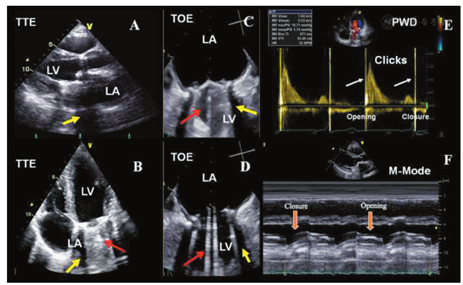

2D TTE是评价PHV首选的影像学检查方法[7,14]。2D TOE检查更多用于对PHV的结构及相关并发症的评价[15]。对于所有PHV功能障碍的患者均推荐进行TOE检查[16,17]。

放大的实时2D图像有利于更清晰显示PHV。M型超声可更好地评价瓣膜运动(瓣叶的快速开放与关闭、阀体的运动度)和对应的时间间隔以及对快速运动的识别。对于二尖瓣位置人工碟瓣运动的评价效果更佳,因为TTE和TOE可在77%和100%的患者中清晰显示二尖瓣的开放和关闭角度[18]。而对于主动脉瓣位置的人工瓣膜,TTE和TOE对单叶碟瓣的开放角度(非关闭角度)的辨识率仅为40%和77%,对双叶机械性瓣膜则仅为13%和35%[18]。由于机械性瓣膜功能障碍间歇性或非周期性出现(间歇性的跨瓣压差升高),因此建议采用连续多个心动周期仔细检测跨瓣压差及碟瓣动度。

生物瓣膜为三瓣叶结构,正常瓣叶为薄层结构(1~2 mm)呈非限制性运动,无脱垂征象。其2D和M型超声表现与自体瓣膜相似,在主动脉瓣位置收缩期和二尖瓣/三尖瓣位置舒张期呈盒状开放。其缝合环和立柱(图3短轴所示3个立柱)呈较强回声,影响了瓣叶的观察(图3A和图3B)。无支架主动脉生物瓣膜或同种异体主动脉瓣与自体主动脉瓣有相似的超声表现,但LV流出道和升主动脉的宽度增加。瓣膜植入后早期,无支架瓣膜插入部位会引起周围组织血肿和水肿。缝合线显示为PHV周围缝合环上的呈线样、较厚、较亮、多个均匀分布的静态结构。如果缝合线较松或较长则可呈一定动度。任何解剖部位的生物瓣膜其3D超声表现与自体主动脉瓣的表现类似,均为3个瓣叶,只不过在二尖瓣或三尖瓣位置植入的人工瓣膜直径较大,而在主动脉瓣或肺动脉瓣位置植入的瓣膜直径较小。

人工瓣膜材料,特别是机械性瓣膜,可产生各种超声波伪像,包括回声影、回响、折射和镜面影像等(图4A,图4B,图4C,图4D,图4E)[14,87]。这些伪像会影响成像质量,尤其是在双瓣膜置换的情况下更加明显。常需要采用多切面甚至离轴切面来克服上述问题,并结合瓣膜周边结构进行分析。通常采用较低的增益设置有利于瓣膜的良好显示。

多数情况下,TTE检查人工二尖瓣/三尖瓣的左右心房侧(LA/RA)将受到声影遮挡,降低了人工二尖瓣或三尖瓣反流(MR、TR)、血栓或赘生物的检出敏感性(图5A,图5B)。而TOE检查可更清晰地显示人工二尖瓣/三尖瓣的LA/RA侧(图5C,图5D)。在主动脉瓣位置,TTE显示瓣膜的后方存在声影(图4A),而TOE显示瓣膜的前方存在声影(图4C,图4D,图4E)[88,89]。对于支架型瓣膜,应仔细调整超声声束与血流平行以避免支架和缝合环引起的伪像[90]。

血流通过功能正常的PHV的血流特征不同于自体瓣膜。前向血流的特征因瓣膜位置、瓣孔的形状和数量不同而各异[7,14,83,84,85,97,98,99]。双重轮廓的多普勒频谱常见于机械性PHV中。PHV血流的多普勒频谱还包括由于阀体开启和关闭所产生的短暂、强回声、快速度的喀喇音信号(图4F,图5E)。在所有切面均应显示瓣孔被彩色血流完全充填(图2B)。